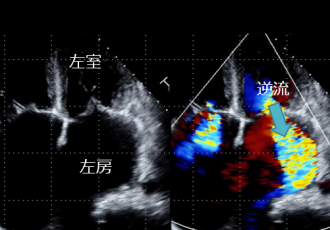

心臓の構造のなかで、左房と左室の間にある膜状の構造を僧帽弁といいます。僧帽弁の働きで左房から左室に送り出された血液は、左室が収縮した際、一方向性に大動脈へ向かい全身に循環します。しかし、僧帽弁に連なる腱が切れたり、左室や左房が過度に大きくなったりすると、僧帽弁がうまく閉じなくなることがあり、逆流が生じます。その量が増えると、息切れ、むくみといった心不全症状や心房細動という不整脈を呈することがあります。このような病状を僧帽弁閉鎖不全症と呼び、高度になると、薬剤治療は功を奏さず、僧帽弁の修復術や人工弁への置き換えが必要となります。

高度の僧帽弁閉鎖不全症